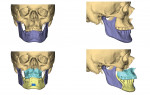

In an MMA procedure, the skeletal advancement is achieved via a maxillary LeFort osteotomy, mandibular bilateral sagittal split osteotomies, and, commonly, a genial tubercle advancement or advancement genioplasty that includes the genial tubercles. These osteotomies are usually planned virtually and stabilized with rigid internal fixation, frequently with 3D-printed titanium plates. Intermaxillary fixation is not required postoperatively.

In the case presented, a 59-year-old male patient had severe OSA (AHI 45), decreased posterior airway space, and concomitant maxillofacial skeletal deformities (Angle class II malocclusion, maxillary and mandibular retrognathia, transverse maxillary hypoplasia, and transverse mandibular hypoplasia) (Figure 1 through Figure 4). Orthognathic surgical planning included tracings of a reconstructed lateral cephalogram to estimate postsurgical esthetic changes after advancements of 8 mm, 10 mm, and 12 mm (Figure 5). It is important to note that facial esthetics may change significantly, and this must be discussed in detail with the patient.

Virtual surgical planning in this case is demonstrated in Figure 6 through Figure 9: preoperative 3D CT imaging and planned surgical bony changes (Figure 6), preoperative 3D CT imaging and planned surgical soft-tissue changes (Figure 7), and examples of prefabricated cutting guides (Figure 8) and plates/screws for the maxilla (Figure 9). Careful attention must be paid to the root apices of the upper posterior and lower anterior teeth, the position of the inferior alveolar nerve and mental foramen, and any potential bony interferences after the reposition of the maxilla and mandible.